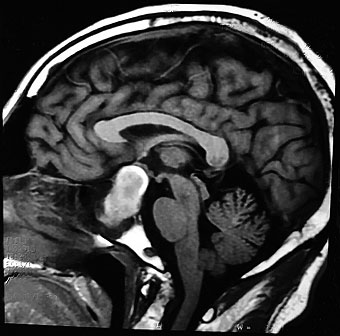

Se establece diagnóstico de macroadenoma hipofisario, y se programa para resolución quirúrgica; sin embargo, dos días previos a su intervención inicia con deterioro neurológico progresivo, caracterizado por somnolencia y dificultad para articular palabras. El médico particular recomienda realizar resonancia magnética nuclear de la silla turca con gadolinio, en la cual se reporta neuritis óptica izquierda, observándose también región hipointensa como manifestación de sangrado hipofisario (figura 2).

La historia natural de la enfermedad en el caso clínico presentado fue secuencialmente típica a lo reportado en la literatura, siendo los síntomas más comunes cefalea, náuseas, vómitos, deterioro de la agudeza visual, oftalmoparesia, hipopituitarismo, mareos, confusión e, incluso, coma.13 El paciente presentó la tríada característica de esta entidad23 y los hallazgos tomográficos característicos de macroadenoma hipofisario; sin embargo, el diagnóstico de apoplejía pituitaria fue discretamente retardado. Un diagnóstico clínico e instrumental completo requiere una neuroimagen adecuada, un examen oftalmológico completo y un panel hormonal completo; las imágenes de tomografía computarizada (TC) pueden resaltar una apoplejía hipofisaria solo en el 25-28% de los casos. Es bien sabido que el adenoma hipofisario, que es isodenso al parénquima cerebral, es difícil de diagnosticar en la TC, incluso en caso de hemorragia. La resonancia magnética cerebral es más sensible y permite el reconocimiento de apoplejía hipofisaria en casi el 100% de los pacientes. En el caso de sospecha diagnóstica de apoplejía hipofisaria se debe preferir la resonancia magnética nuclear,13 en la cual se pueden llegar a evidenciar imágenes con forma de "figura de ocho" o "apariencia de muñeco de nieve", ya que la dureza del diafragma de la silla turca crea en el tumor un istmo.24